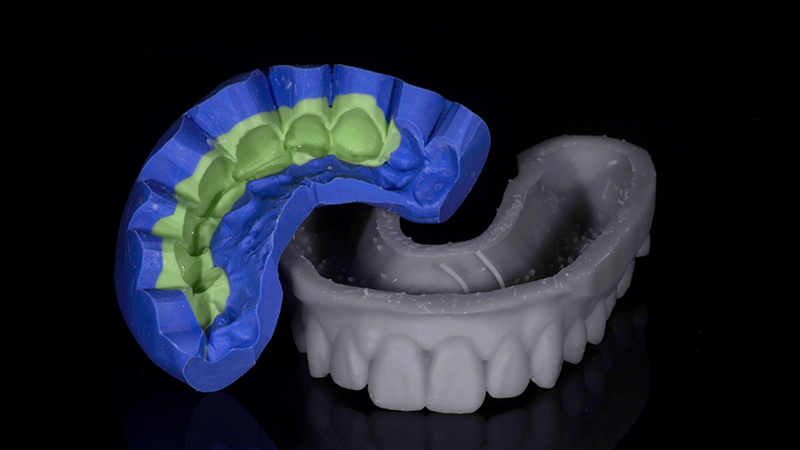

In questo caso, testo il potenziale estetico del progetto, creo un mock-up, prototipando un modello in resina con la nuova morfologia e una mascherina in silicone per eseguire la prova direttamente nella bocca del paziente (Fig. 6d, Fig. 6e). Simulo il nuovo sorriso del paziente, verificandone armonia e proporzionalità (Fig. 7).

È stato preparato un piano di trattamento definitivo in 4 fasi della durata di 8 mesi.

Modello STL con la nuova morfologia

Fig. 6d - Modello STL con la nuova morfologia.

Modello prototipato e indice in silicone

Fig. 6e - Modello prototipato e indice in silicone.

Mock-up e impatto estetico sul viso del paziente

Fig. 7 - Mock-up e impatto estetico sul viso del paziente.